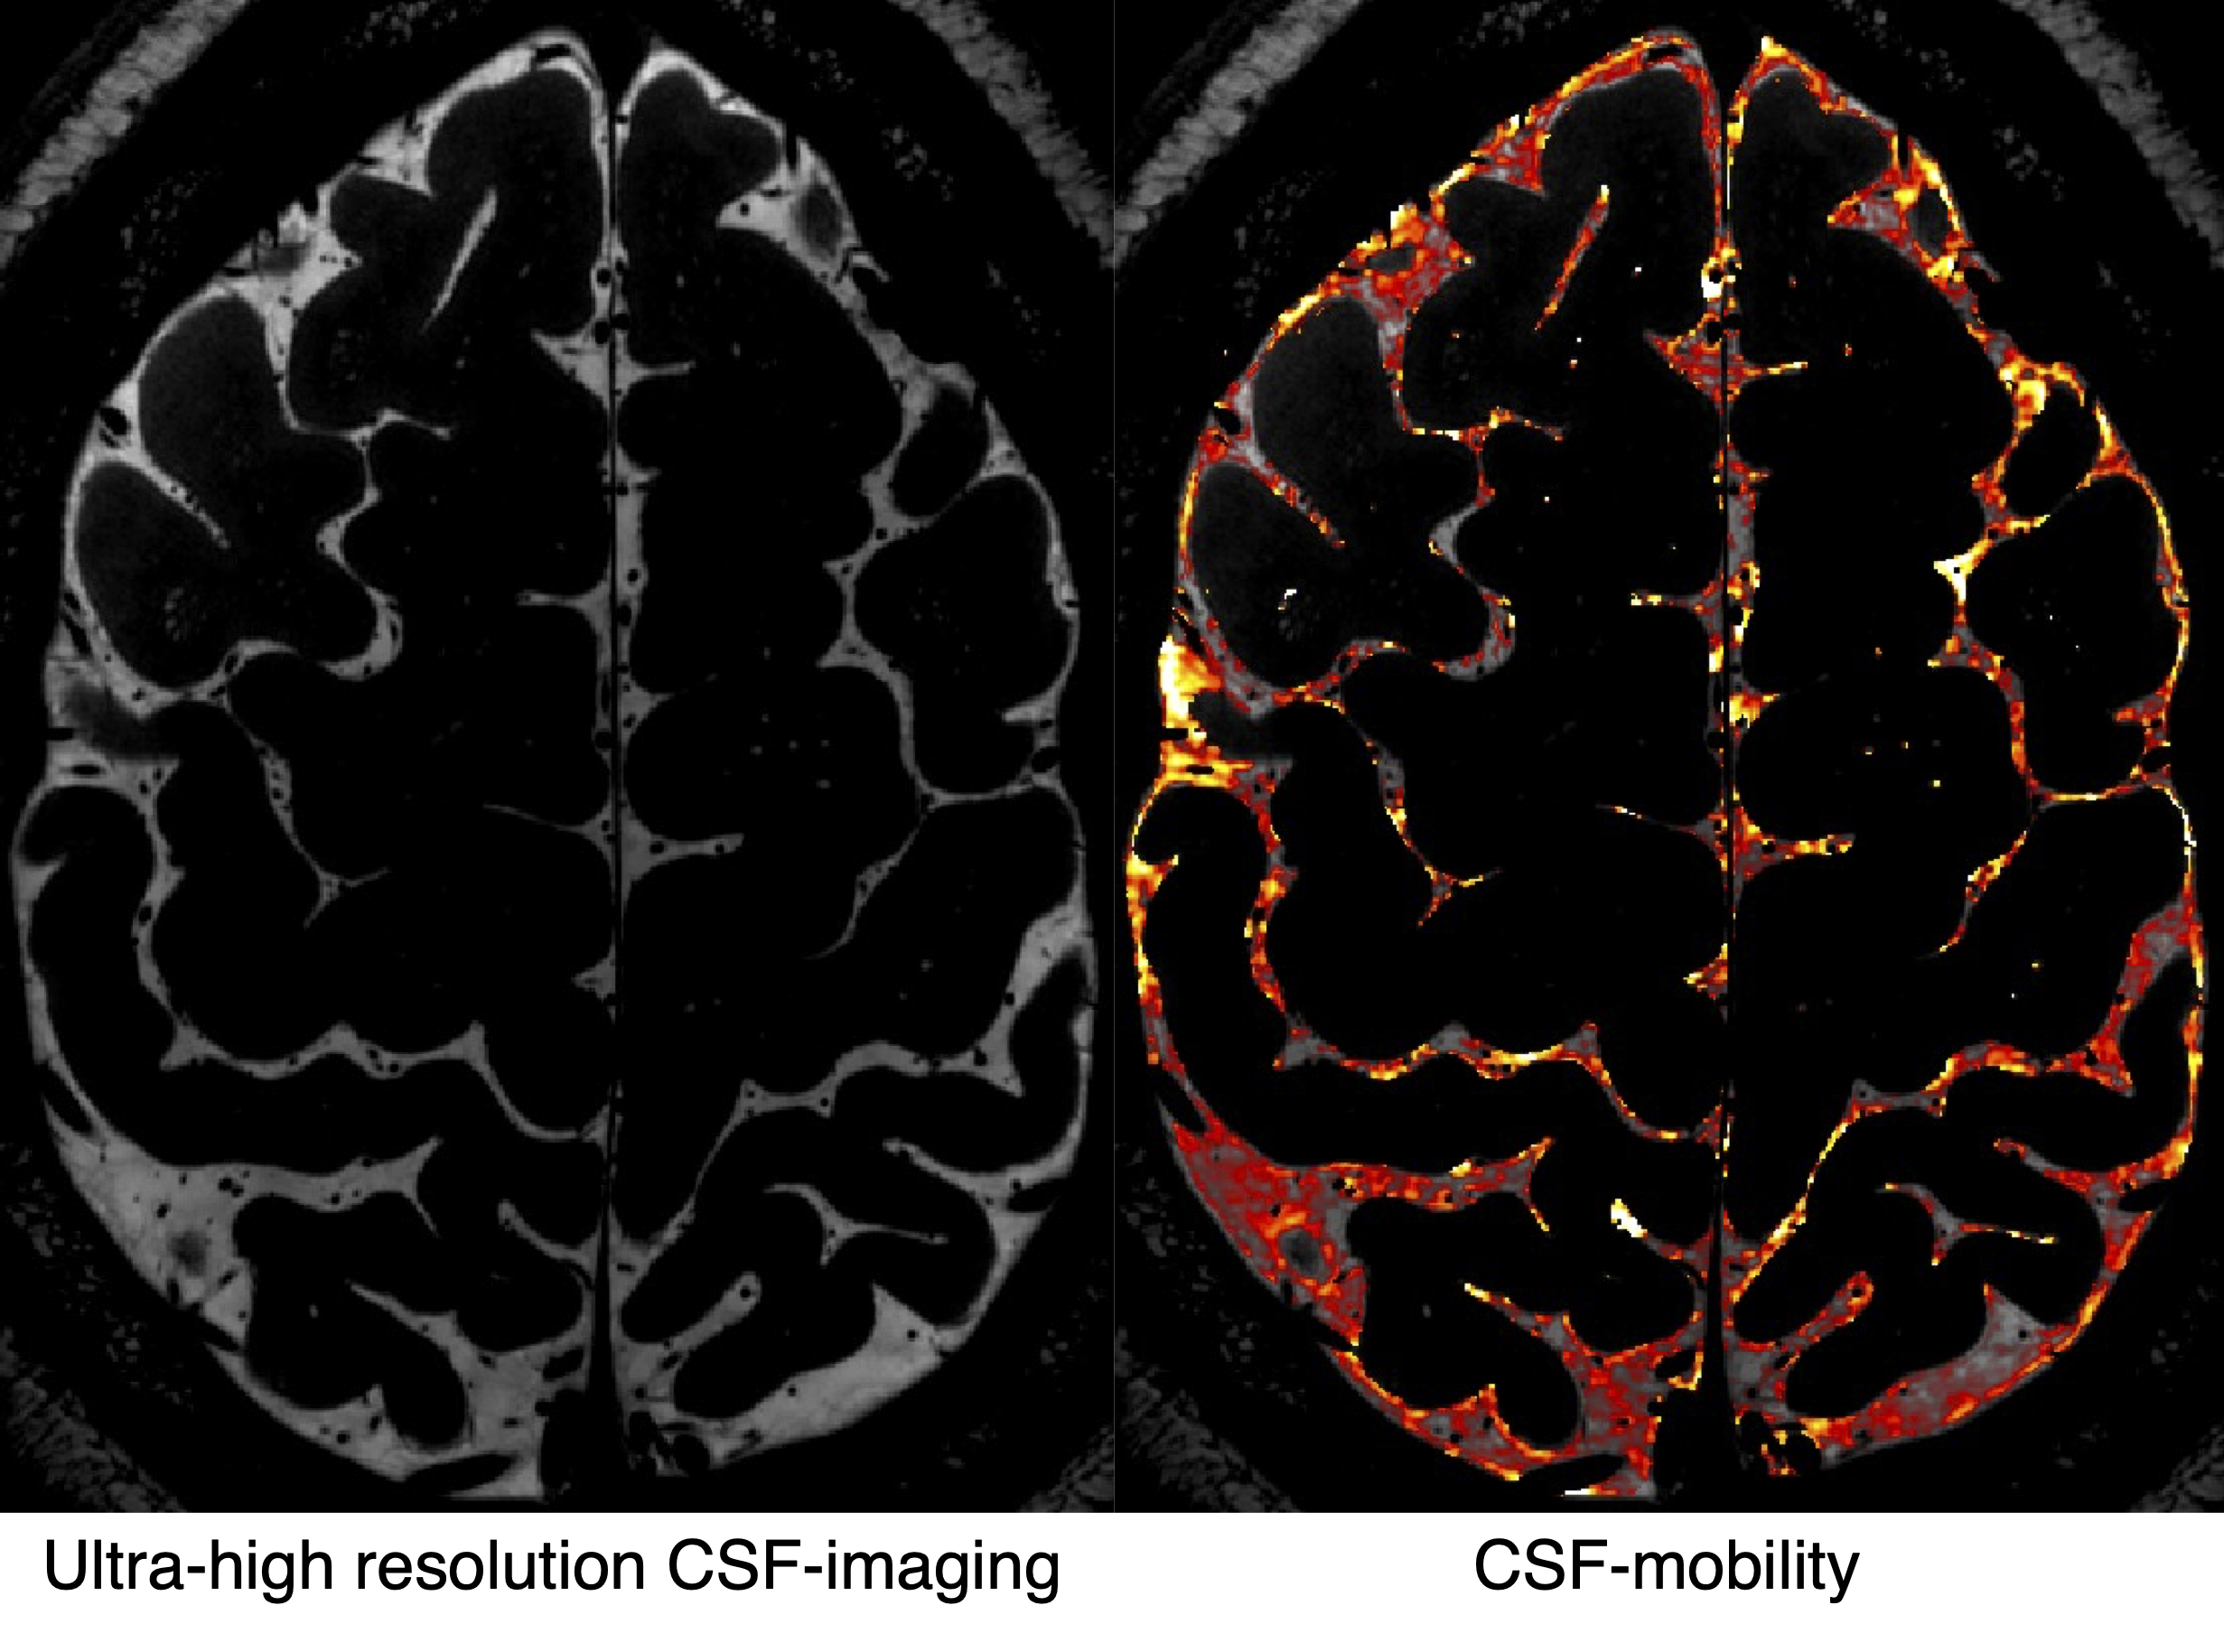

Much of this exchange takes place in the subarachnoid space surrounding the brain, where it is thought to drive the glymphatic system. Yet the forces that drive these flows, and the structures that shape them, remain poorly understood in humans: studying them has so far demanded invasive procedures or ex-vivo tissue. The discovery of the glymphatic system has since accelerated the development of non-invasive neurofluids MR. The neurofluids research group utilize these advances, sequences such as CSF-STREAM and ultra-high resolution CSF imaging, in an iterative loop between a basic-research arm and a clinical arm, each feeding the other.

In the basic-research arm, we study the function and structure of CSF flow in the subarachnoid space, with particular focus on the perivascular subarachnoid space, where exchange between CSF and brain tissue is thought to occur. Using ultra-high-field (7 T) MRI and purpose-built sequences such as CSF-STREAM and phase-contrast MR spectroscopy, we develop and optimise methods to measure these flows and identify the structural features and biomarkers worth following in patients.

The CCLEAR7T is a collaboration between DRCMR and Danish Headache Center to use ultra-high field MRI in combination with a newly developed MRI sequence, CSF-STREAM, to measure CSF circulation as well as structural alterations in fine CSF pathways around the brain. We aim to gain unique knowledge on how the brain and CSF regulation are altered when SIH decreases intracranial pressure and whether these alterations reverse after successful treatment. Due to its mechanical nature and reversibility, SIH is a unique condition to study CSF dynamics and their influence on brain waste clearance safely in humans. The results will also inform a state-of-the-art diagnostic evaluation of SIH.